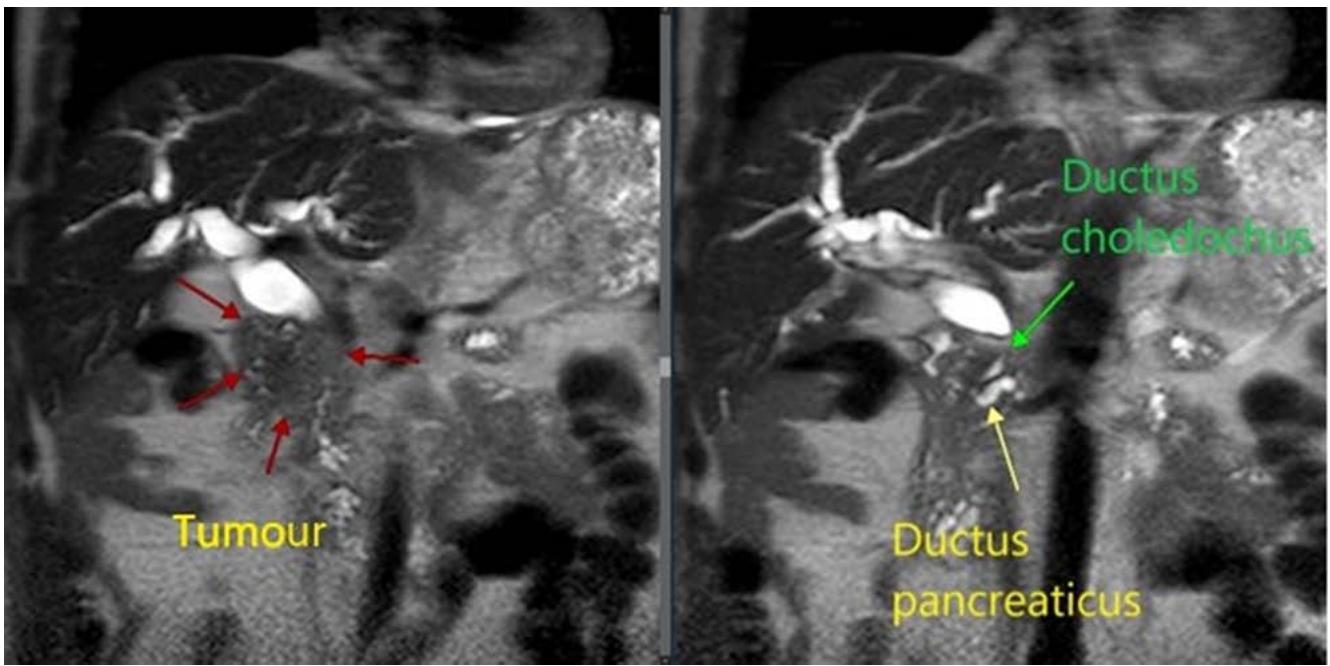

Fig. 7: MRI-characteristics of a tumour of the head of the pancreas Fig. 6: Device for trephine biopsy of tumours of the head of the pancreas and the distal common bile ductbyE.B.Revazov-Ts.S.Khutiev

To determine the technical aspects of performing trephine biopsy, we performed a continuous retrospective analysis from a database of 100 contrast-enhanced MRIs of the abdominal cavity in patients with a tumour of the head of the pancreas and biliary hypertension (Fig. 7). Studied the size and preferential localization of the tumour in relation to the hepaticocholedochus (HC), its relationship to the main pancreatic duct (MPD) and duodenum (DU). The age of the patients was 35-90 years, with average of $65 \pm 1,13$. Men - 54 (54%), women - 46 (46%).

<table><tr><td>Sign</td><td>Minimum</td><td>Maximum</td><td>Average</td></tr><tr><td>Tumour size (mm)</td><td>11</td><td>89</td><td>35.4±1,53</td></tr><tr><td>Diameter of hepaticocholedochus (HC)(mm)</td><td>7.5</td><td>35</td><td>15,6±0,51</td></tr><tr><td>The length of the tumour narrowing of the HC(mm)</td><td>4</td><td>50</td><td>27±1,1</td></tr><tr><td>Hepaticocholedochus angle (degrees)</td><td>80</td><td>162</td><td>115,3±1,69</td></tr><tr><td>Diameter of the main pancreatic duct (MPD)(mm)</td><td>2</td><td>18</td><td>7,3±0,37</td></tr><tr><td>Distance from the level of the HC block to the level of the MPD block (mm)</td><td>1</td><td>63</td><td>11,9±1,02</td></tr><tr><td>Length from the proximal border of the HC block to the duodenum (mm)</td><td>14</td><td>52</td><td>30,8±0,91</td></tr></table>

Tumour size varied from 11 to $89\mathrm{mm}$, averaging $35,4 \pm 1,53\mathrm{mm}$. According to the TNM system in stages $T_{1} - 4$, $T_{2} - 60$, $T_{3} - 32$, $T_{4} - 4$ patients. Signs of germination in the duodenum and MDP were noted in 18 (18%) patients; limited to invasion of parapancreatic tissue in 7 (7%) patients. Enlarged regional lymph nodes in 14 (14%) patients. Distant metastases were detected in 28 (28%) patients. Of them: $T_{1} - 2$, $T_{2} - 10$, $T_{3} - 15$, $T_{4} - 1$.

The diameter of the hepaticocholedochus (HC) ranged from 7,5 to $35\mathrm{mm}$, on average $-15,6\pm 0,51\mathrm{mm}$; the length of the tumour narrowing of the HC is from 4 to $50\mathrm{mm}$, the average is $27\pm 1,1\mathrm{mm}$. In 19 (19%) cases, an intact distal part of the common bile duct was identified extending from 5 to $36\mathrm{mm}$. The length from the proximal border of the HC block to the duodenum along the HC axis is $14 - 52\mathrm{mm}$, on average $-30,8\pm 0,91\mathrm{mm}$.

The HC angle in the distal third was $80 - 160^{\circ}$ with an average of $115,3\pm 1,69^{\circ}$. The magnitude of the angle depended on the predominant localization of the tumour, the degree of biliary hypertension and the associated elongation of the HC and its tortuosity. Currently, there is no clear understanding of the dependence of technical actions on a simple statement of the value of the angle HC. The opinion of an individual approach to this parameter and its further study remains.

The diameter of the main pancreatic duct (MPD) is from 2 to $18\mathrm{mm}$, on average $-7,3 \pm 0,37\mathrm{mm}$. The absence of pancreatic hypertension was noted in 14 $(14\%)$ patients, including 4 $(4\%)$ with a tumour size more than $40\mathrm{mm}$. 27 $(27\%)$ had MPD from 3,5 to $6\mathrm{mm}$ and 57 $(57\%)$ had $6\mathrm{mm}$ or more. In 2 $(2\%)$ MPD was not possible to visualize due to the extensive of the tumour process in the pancreas.

The distance from the HC block level to the MPD block level ranged from 1 to $63 \mathrm{~mm}$, with an average of $11,9 \pm 1,02 \mathrm{~mm}$. In 26 (26%) patients this distance is less than $7 \mathrm{~mm}$ and in 13 (13%) of them the

MPD diameter is 6mm or more. Erosion of the internal contour HC in the area of the block was detected in 35 (35%), of which in 17 (17%) – like a "writing pen", in 9 (9%) – on the lateral side, in 9 (9%) – on the medial side; in 65 (65%) a "transverse block" is determined. There is no unambiguous connection between the predominant localization of the tumour and the size of HC contour usuration. Preferential location of the tumourabout HC: antemedial – 49 (49%), antegrade – 18 (18%), circular – 20 (20%), medial – 6 (6%), antelateral – 5 (5%), latero-antemedial – 2 (2%). In 67 (67%), the tumour thickness anterior to the HC lumen was more than 10 mm (Fig.8, 9, 10).